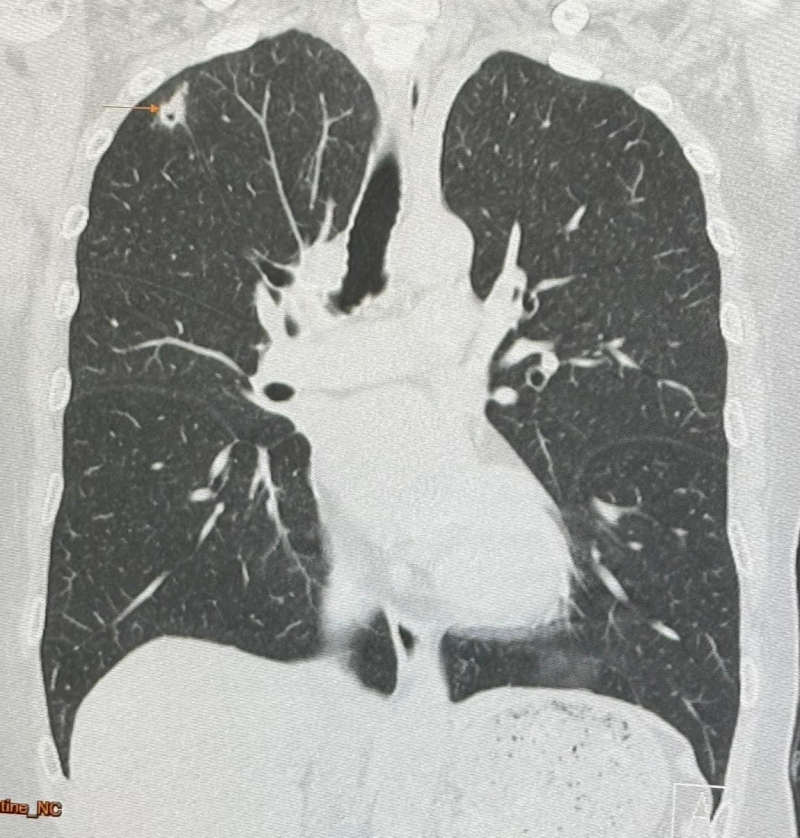

นพ.มนูญ ลีเชวงวงศ์ แพทย์เฉพาะทางด้านโรคระบบการหายใจ รพ.วิชัยยุทธ โพสต์ ผู้ป่วยหญิงอายุ 52 ปี บ้านอยู่ กทม. ปกติแข็งแรงดี ไม่ไอ ไม่มีไข้ ไม่เบื่ออาหาร น้ำหนักไม่ลด ไม่ปวดหัว ไม่เคยสูบบุหรี่ ไม่มีโรคประจำตัว ไปตรวจร่างกายประจำปี วันที่ 12 พฤษภาคม 2567 เอกซเรย์ปอด พบก้อนเล็กๆ เกิดขึ้นใหม่ที่ปอดขวากลีบบน (ดูรูป) เอกซเรย์ปอดก่อนหน้านั้น 1 ปีปกติ ทำคอมพิวเตอร์ปอดพบก้อนขนาด 0.9 × 0.9 × 1.7 เซนติเมตร เห็นโพรงอยู่ข้างในก้อนที่ปอดขวากลีบบน (ดูรูป) ตรวจเลือดไม่ติดเชื้อเอชไอวี